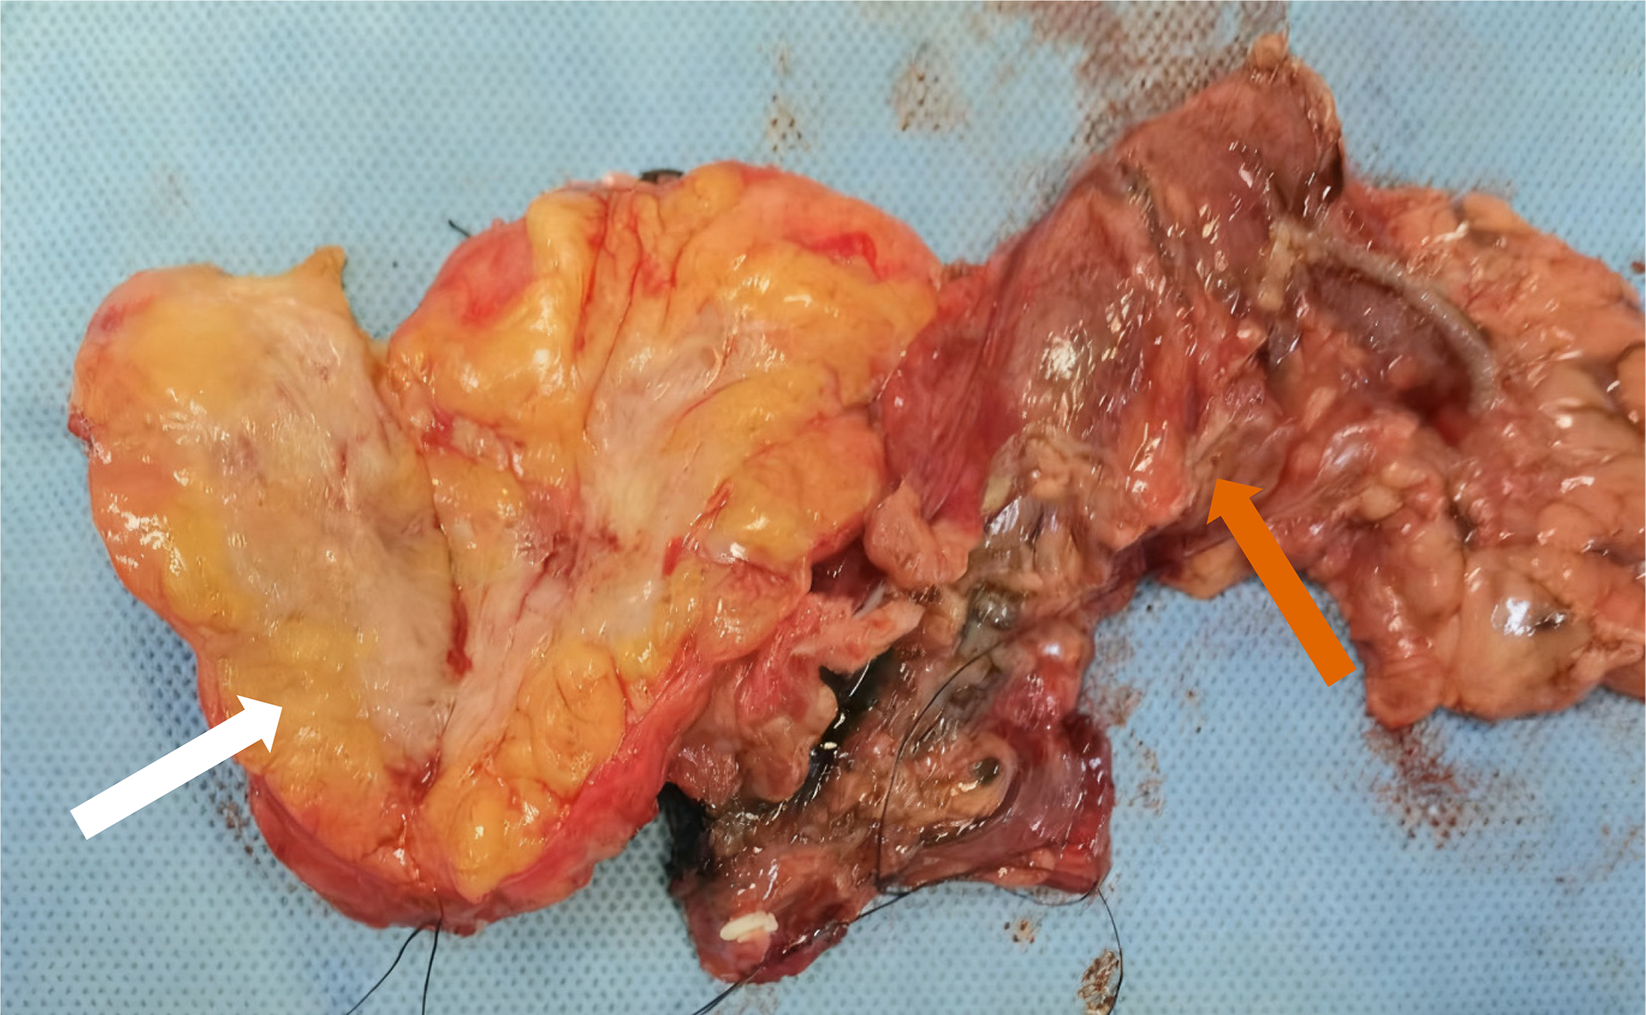

Figure 4 Surgical resection of gross specimens.

Pancreatic tumor (white arrow) and colon (orange arrow).